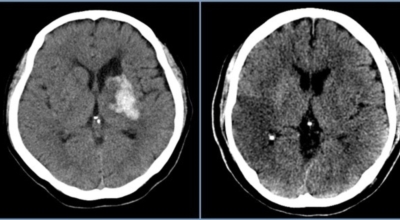

뇌경색 초기증상이 나타나면 가장 중요한 것은 빠른 인지와 빠른 치료예요. 뇌세포는 뇌혈관이 막히는 순간부터 빠르게 손상이 진행이 되고 재생은 어렵기 때문입니다. 뇌와 연관된 질병은 골든타임을 놓치지 않는 것이 제일 중요해요.

큰 뇌혈관이 막힌 경우라면 발생한지 4시간 반 안에 정맥 내로 혈전 용해제를 투여해 막힌 혈관을 뚫어주게 되고 6시간 이내라면 직접 동맥 내 시술을 통해 혈관을 막은 혈전을 직접 제거하는 혈전제거술을 시행하게 되는데요.